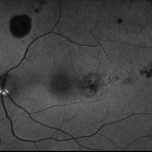

Retinal Microaneurysm FA Image

May 12 2025 by Briana Hernandez

Fluorescein Angiogram OS Image of Retinal Microaneurysm in 81-year-old female BRVO patient.

Photographer: Briana Hernandez

Imaging device: Optos

Condition/keywords: FA